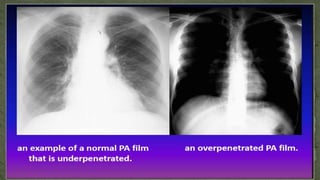

G. Penetration

• To check the penetration, look at the lower part of the cardiac shadow

• The vertebral bodies should be barely visible through the cardiac shadow at this

point.

• If they are clearly visible then the film is over penetrated and you may miss low

density lesion.

• If you cannot see them at all then the film is under penetrated and the lung fields

will appear falsely opaque (white).

• The left hemidiaphragm should be visible to the edge of the spine

• When comparing X-Rays first determine if the level of penetration is similar.